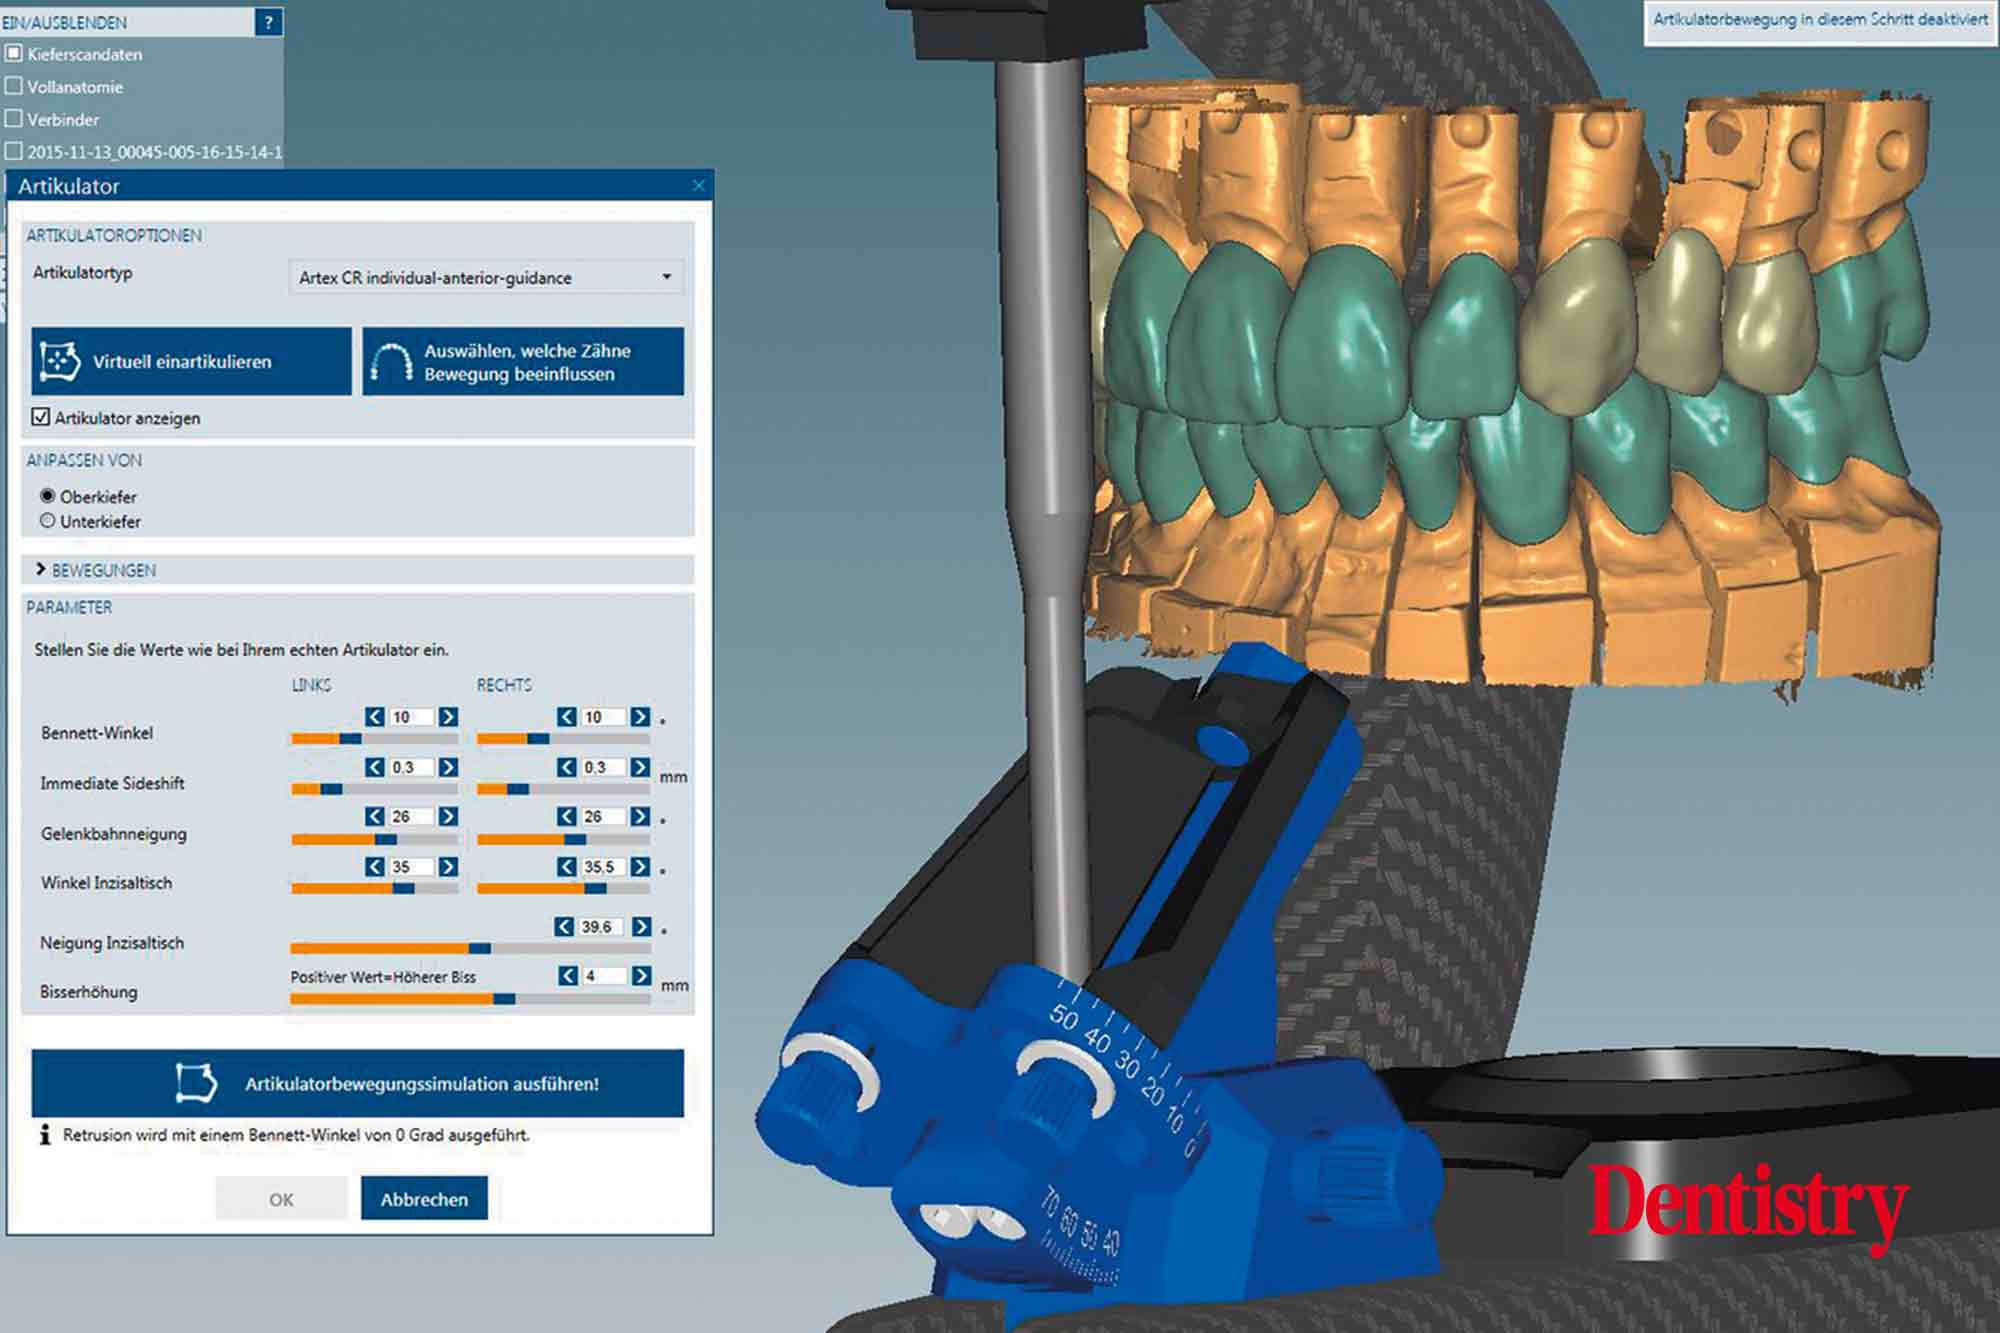

The scanned models were evaluated on a virtual 11 articulator. Temporary Ceramill PMMA (Amann Girrbach) transparent acrylic crowns were CAD planned (Figures 3a to 3d).

Patient data including condylar movements were recorded by the software. Using the Initial situation software’s customised incisal guide unit, the incisal guide pin was adjusted on the splitex plate to the desired cuspal inclinations on the virtual temporary crowns (Figure 4).

All patient parameters including condylar inclination were transferred to the Ceramill Artex articulator and the lateral and protrusive excursions were established while having no contact with the anterior teeth (Figures 5 to 8).